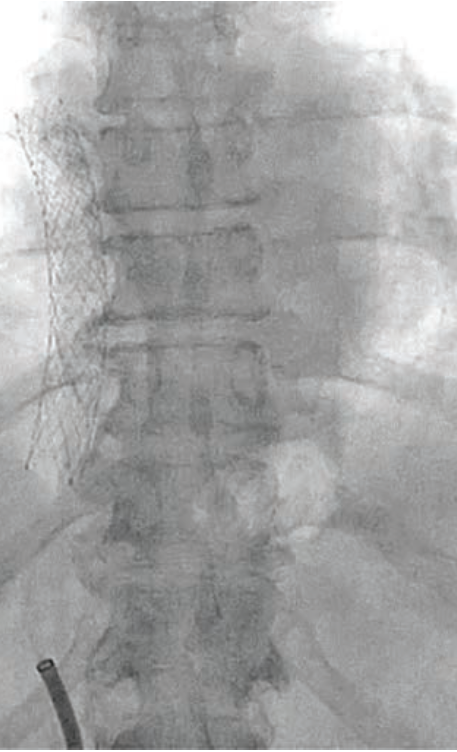

The cath lab team began by deploying the cerebral protection device filters in the right brachiocephalic and left common carotid arteries via a 6 French (F) radial sheath. Access to the right common femoral artery was obtained with ultrasound and micropuncture. Following a pre-closure device, a 12F sheath was inserted. The LVAD speed was 0.8 L/min, and the patient’s mean arterial pressure (MAP) was 75 mmHg with pressors. The outflow graft was cannulated with a Stiff Glidewire and a 5F GlideCath (both Terumo Interventional Systems). The shorter sheath was exchanged for a Shuttle sheath (Cook Medical), and an injection was performed through the GlideCath. This image showed a clear obstruction at the bend relief space, causing the kink and low flows.

An 11 mm x 16 mm covered stent was placed, followed by an .035-inch 10 mm x 40 mm balloon, but the kink remained. A 12 mm x 40 mm percutaneous transluminal angioplasty (PTA) balloon was inserted and the kink gave. However, the flows did not improve and, in fact, temporarily dropped.

The precipitous drop in flow was caused by the pannus shifting toward the proximal outflow graft near the pump housing. The team quickly deployed an 11 mm x 16 mm stent to support the proximal graft, followed by a 12 mm x 40 mm PTA balloon. The patient’s LVAD flow improved to a remarkable 4.5 L/min.